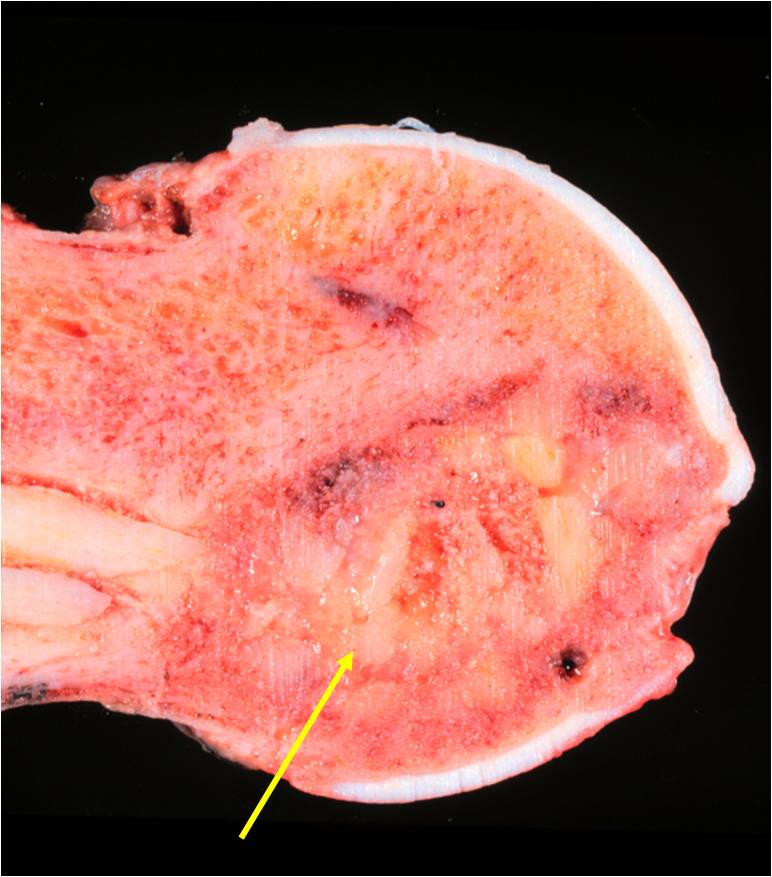

Gross Pathology

- Cut surface

- Typically lacks appearance of conventional chondrosarcoma

- Usually red, soft and granular

- Possibly multiple cysts

- Small areas of gray or white cartilage may be irregularly interspersed